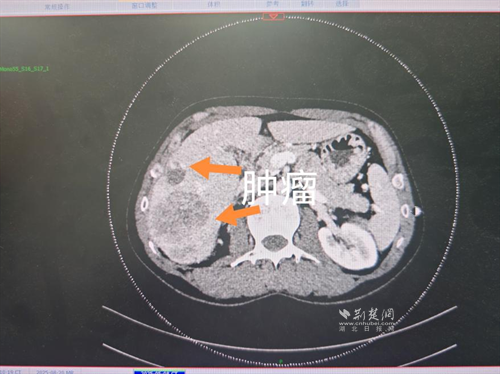

經(jīng)過肝膽外科牽頭組織的多學科MDT會診,團隊確認其適合接受當前國際先進的釔90樹脂微球選擇性內放射治療。治療僅一個月后,患者病灶即從10cm縮小至6cm;術后六個月復查顯示,病灶體積進一步縮小近40%,影像學檢查提示完全緩解,臨床分期成功轉化,達到手術切除標準。